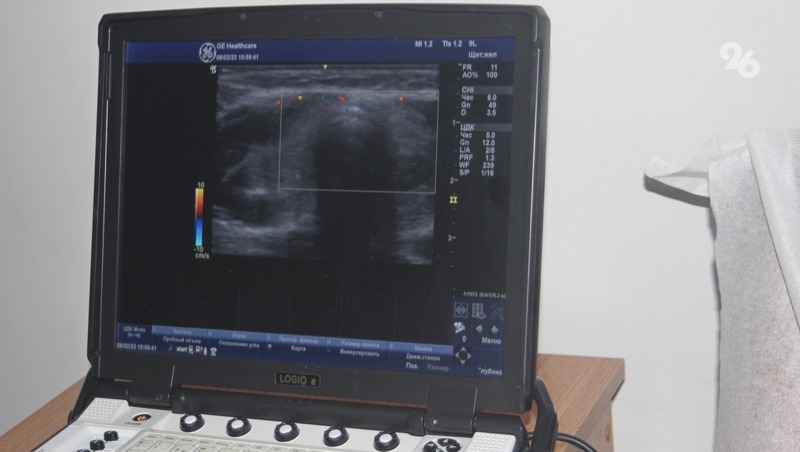

В диагностическом центре Невинномысска в эти дни работают более 20 врачей различных онкоспециальностей, они проводят медицинские осмотры работников промышленных предприятий города.

Готовиться к масштабному медицинскому проекту, проходящему сегодня в крае, начали ещё в 2022 году. Незадолго до приезда «Онкопатруля» на градообразующих предприятиях Невинномысска провели анкетирование, которое прошли порядка 4 тыс. человек. Кроме того, ещё до начала проекта у желающих принять участие в программе взяли первичные анализы, женщинам провели маммографию. В результате 300 человек пригласили на дальнейший полный медосмотр.

Медики Невинномысска получили новые знания благодаря проекту «Онкопатруль»В рамках «Онкопатруля» в Невинномысске не только проводится медосмотр, но и мастер-классы, круглые столы для медицинского персонала первичного звена. На мастер-классах для врачей различных направлений рассматривают реальные случаи на примере пациентов, прошедших первичную диагностику при подготовке к мероприятиям.